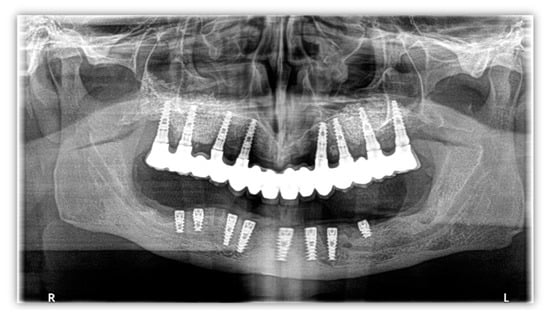

2. Case Report